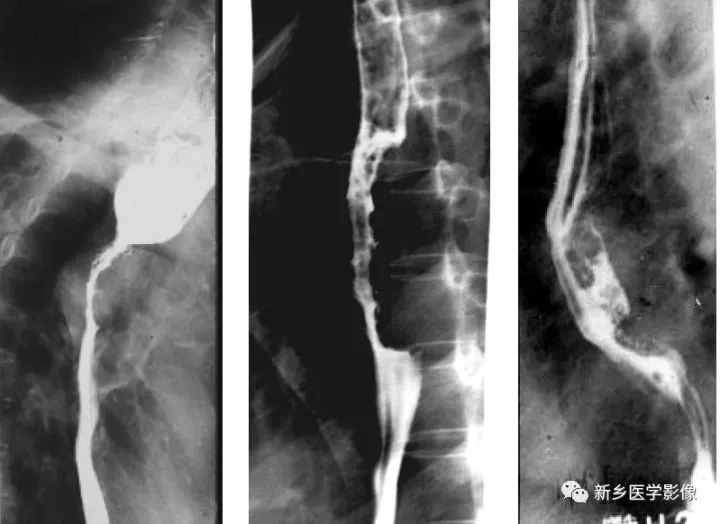

中晚期食管癌鋇餐造影圖像

a、浸潤型食管癌,顯示食管上段向心性狹窄,邊緣不規則,局部見軟組織腫塊,狹窄以上食管擴張

b、增生型食管癌,食管中段偏心性不規則充盈缺損,邊緣不規則

c、潰瘍性食管癌,食管中段偏心性腫塊,局部見腔內龕影